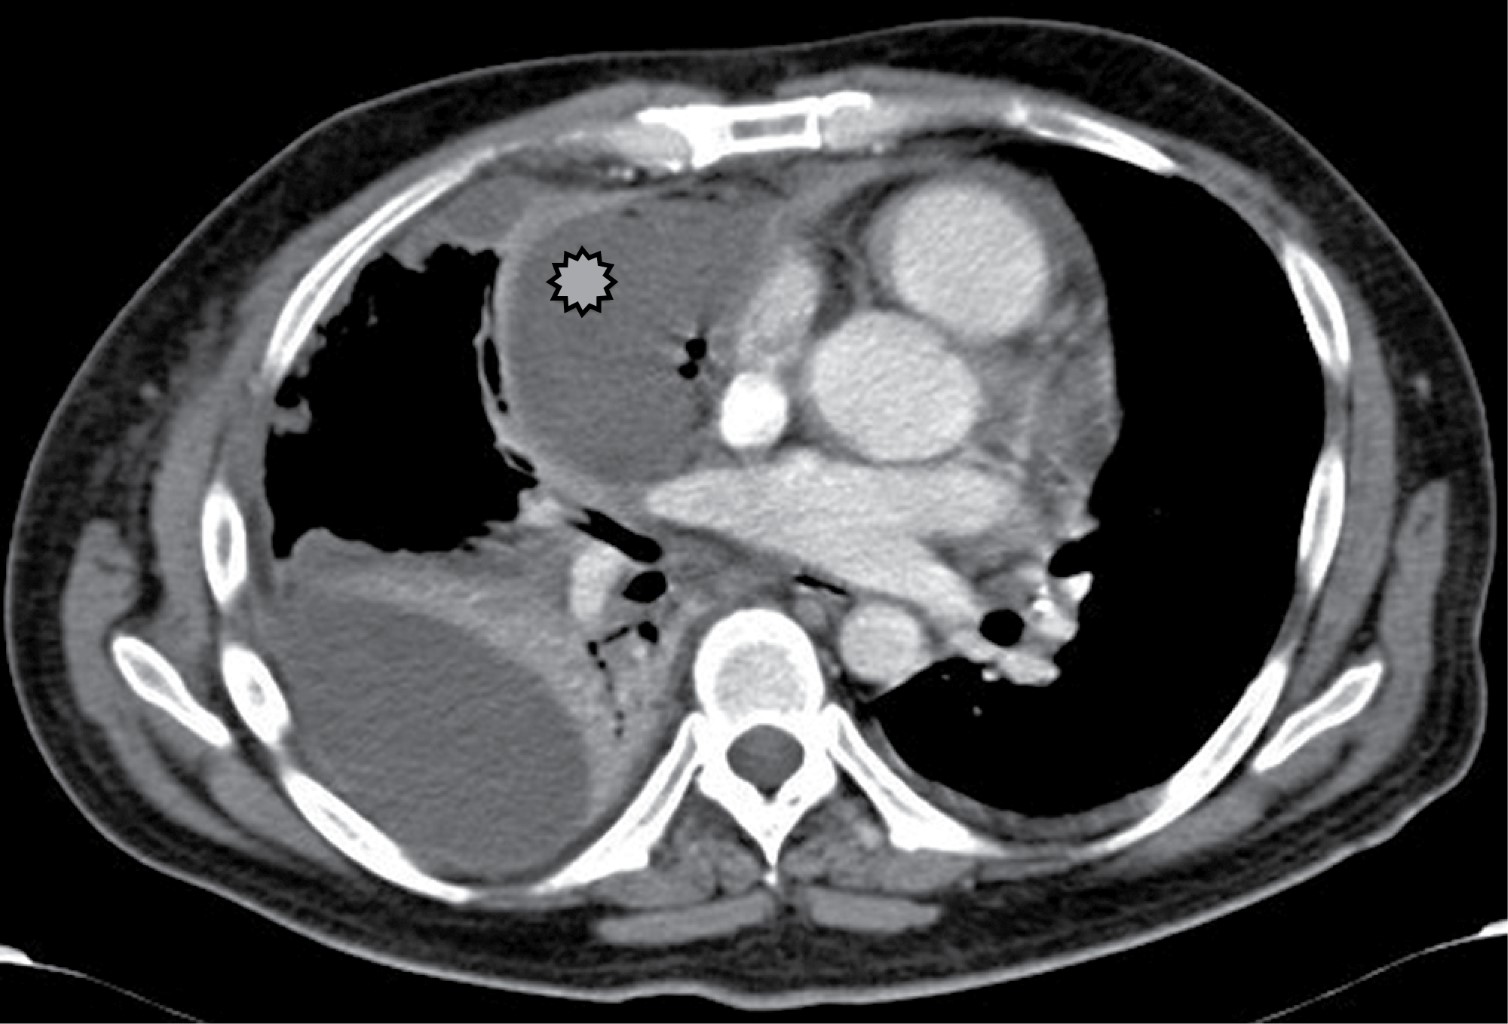

La linfadenopatía mediastinal ocurre en 7% de los adultos con tuberculosis, aunque el crecimiento de ganglios linfáticos es más común en SIDA. La linfadenopatía puede demostrar baja atenuación central, estas áreas de baja densidad dentro de los ganglios linfáticos corresponden a necrosis caseosa (Figura 1).2 La zona paratraqueal derecha es la más común, pero puede afectar el mediastino anterior o el hilio. Los ganglios linfáticos pueden coalescer en masas pobremente definidas y adherirse a las estructuras vasculares adyacentes y estructuras mediastinales.

Los hallazgos tomográficos incluyen colecciones líquidas, gas en el mediastino, incremento en la atenuación de la grasa mediastinal, ensanchamiento mediastinal, derrame pleural, derrame pericárdico y presencia de linfadenopatía, en asociación con anormalidades periesternales tales como edema de tejidos blandos, separación esternal con resorción ósea marginal, esclerosis y osteomielitis (Figura 2). Los primeros dos hallazgos son caracterizados en la literatura como altamente positivos.7